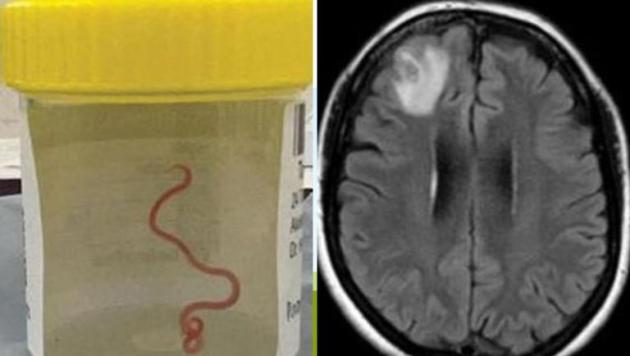

Il verme nella testa della donna le causava da anni febbre e depressione. L'operazione eseguita in Australia ha rimosso il parassita di 8 centimetri per la prima volta osservato in un essere umano

L'inatteso ospite nel cervello della 64enne, infatti, è un esemplare di 8 centimetri di Ophidascaris robertsi, comunemente ritenuto prediligere come "ospiti" i pitoni. La donna è stata immediatamente operata, con i medici che sono riusciti ad estrarre vivo il parassita, ed è ora ricoverata in buone condizioni presso l'ospedale di Canberra.

Nei mesi successivi, tuttavia, la salute della donna peggiora: ai mali che già la colpivano, infatti, iniziano a sommarsi episodi di amnesia e depressione. Nel 2022, quindi, un nuovo ricovero, questa volta all'ospedale di Canberra. Una fortuna, per la 64enne, perché in questo secondo istituto tra le varie analisi è stata anche sottoposta ad una risonanza magnetica al cervello, i cui risultati hanno lasciato senza parole i medici.